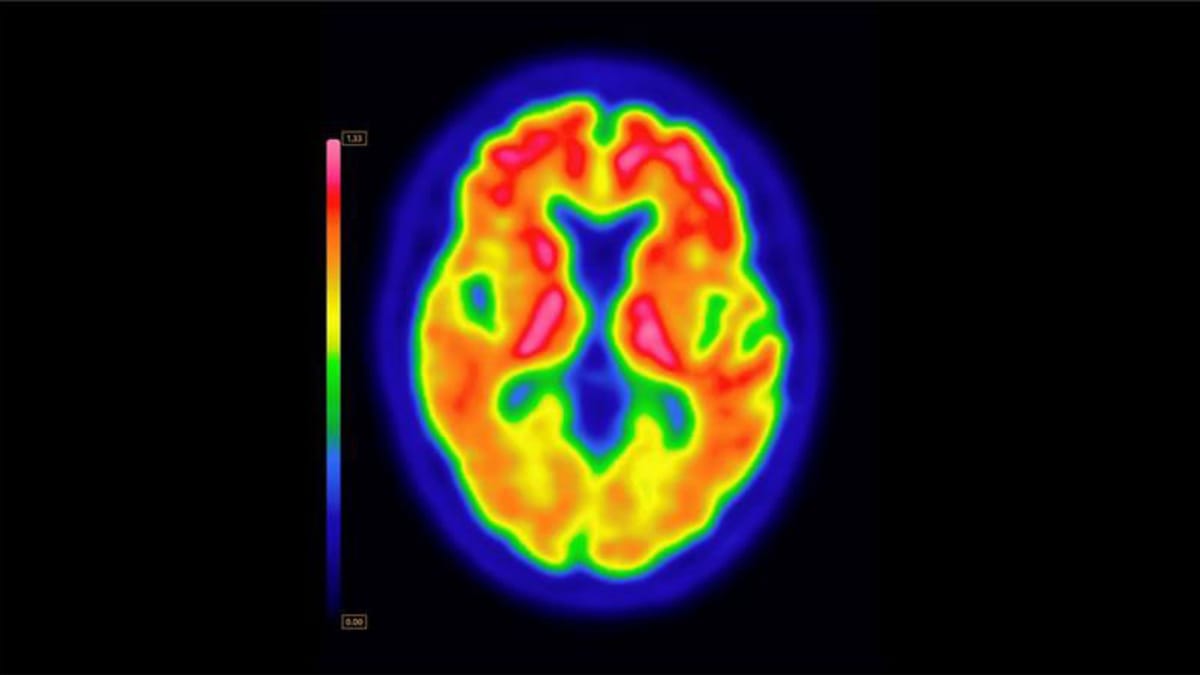

منطقة الحصين

وقد تيقنت هذه الدراسات من مسألة واحدة وهي أنه إذا كانت الخلايا العصبية تتكون داخل مخ الانسان في مرحلة البلوغ، فلابد أن ذلك يحدث في منطقة الحصين، وهي جزء عميق داخل المخ يضطلع بدور رئيسي في عملية الذاكرة وتخزين المعلومات.